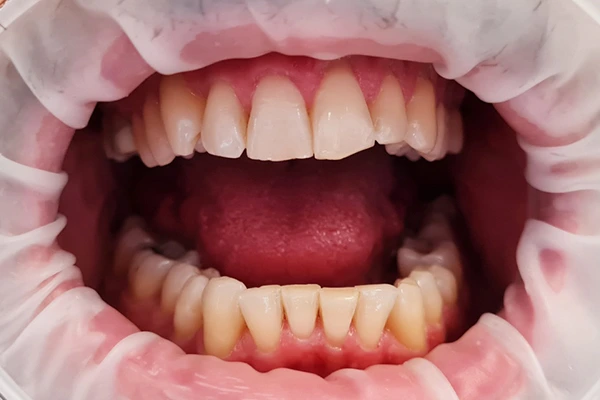

PRIJE I POSLijE

I can’t change the world, but I can change your smile!